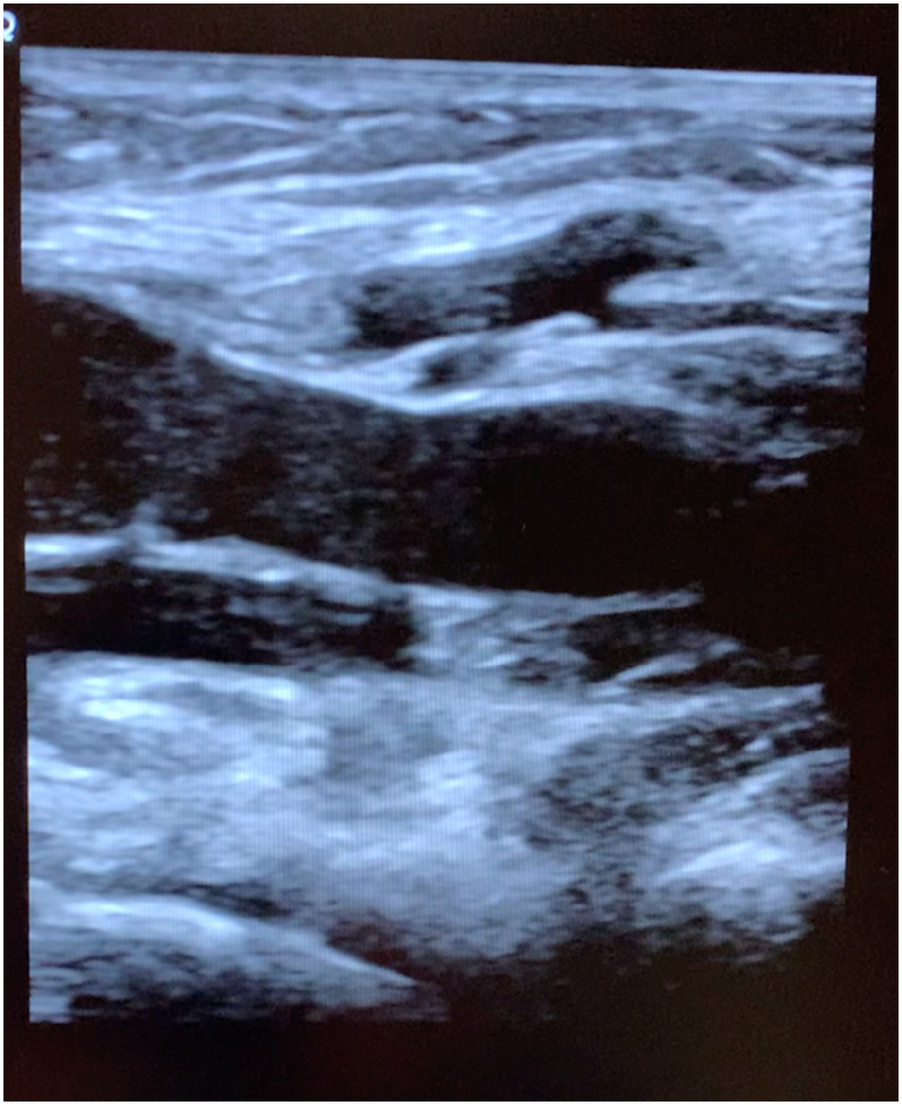

Figure 3

Longitudinal popliteal vein 10 min after exposure demonstrating residual rouleaux.

The subject walked for 5 min after the second scan to see if the rouleaux formation would dissipate with exercise and then reimaged a 3rd time. The final imaging cine loop (10 min after exposure) demonstrate continued rouleaux formation, but the conspicuity of the aggregates had diminished as compared to the immediate post exposure images (Figure 3).